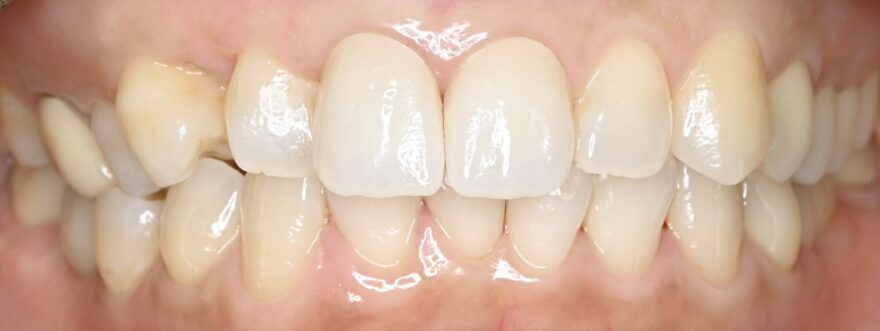

奥歯のインプラントと前歯のセラミックのコンビネーション治療例

治療後のレントゲン写真

この症例の治療費

前歯プレミアムセラミック2本→330,000円(税込)

《1本あたり165,000円(税込)》

ファイバーコア1本(神経ない歯への補強材)→22,000円(税込)

奥歯インプラント2本→880,000円(税込)

《1本あたり440,000円(税込)》

奥歯用セラミック3本→330,000円(税込)

総額 1,232,000円(税込)